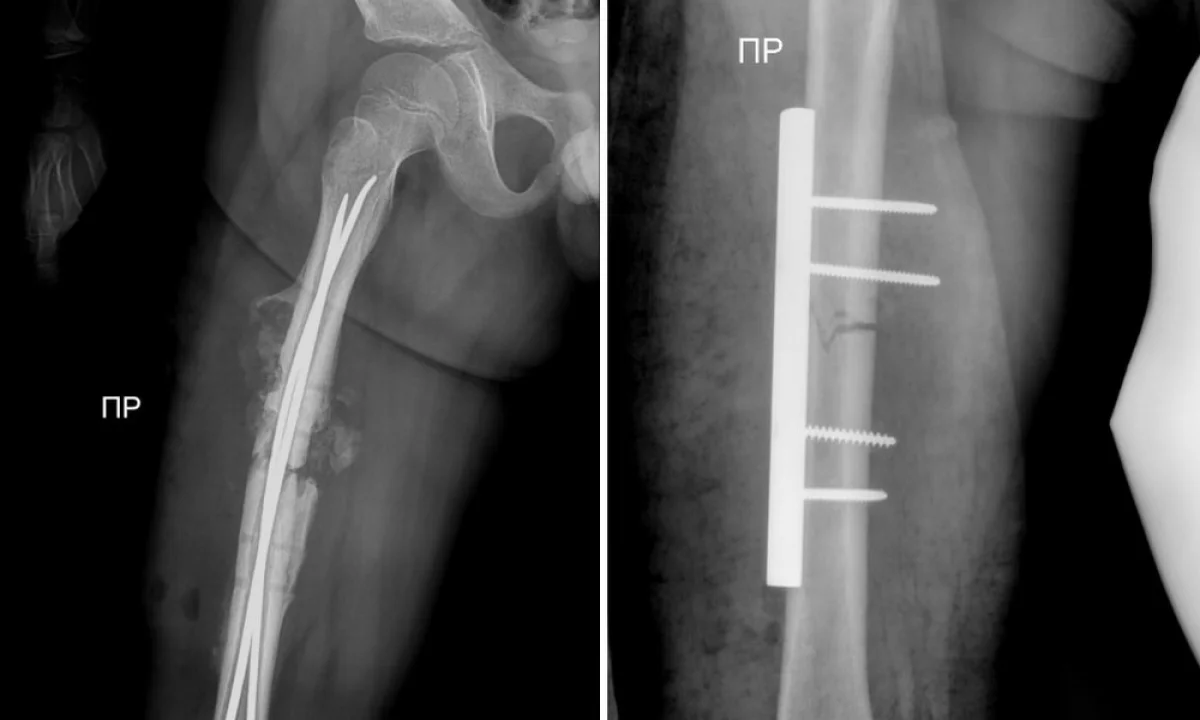

В стенах областной детской больницы впервые была проведена операция по установке гибких фиксирующих стержней, рассказал актауский общественник Азамат Сарсенбаев.

В августе этого года, по словам Азамата Сарсенбаева, ребёнка сбила машина. У мальчика сломалась кость.

Тогда на базе детской больницы в области бедра ему установили металлические фиксаторы.

На этой неделе мальчик неудачно упал и у него, к сожалению, сломались фиксаторы.

Врачам на этот раз пришлось повторно проводить операцию.

В течение часа детский хирург Курман Кайранов успешно заменил металлический на более современный гибкий стержень.

- Преимущество гибкого стержня заключается в том, что теперь при переломах больше не требуется делать большие разрезы в конечностях для установки фиксирующих стержней. Достаточно лишь сделать разрез в один сантиметр и вводить гибкий стержень под рентгеновским контролем, - рассказал Курман Кайранов.